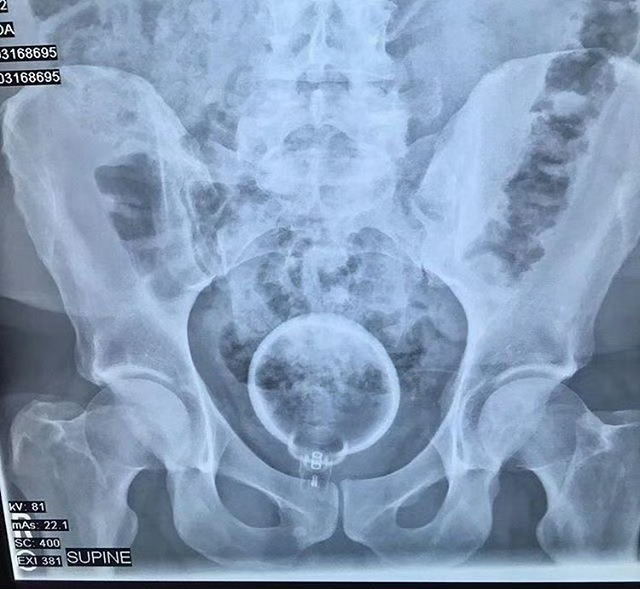

据统计,在急诊室中,男性“失物招领”的情况是女性的40倍,大部分失物是在肠道中被发现的,而且花样繁多……